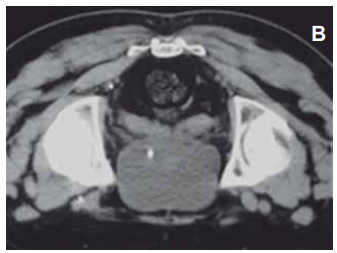

As imagens de tomografia computadorizada podem ser analisadas em diferentes cortes ou formatações:

Enunciado 4560251-1

(https://www.scielo.br/j/rb/a/Z9LkbsH6Qb6vLHm3HJP5Qcp/?lang=pt)

A imagem apresentada retrata a região da pelve, e é um estudo realizado em corte no plano